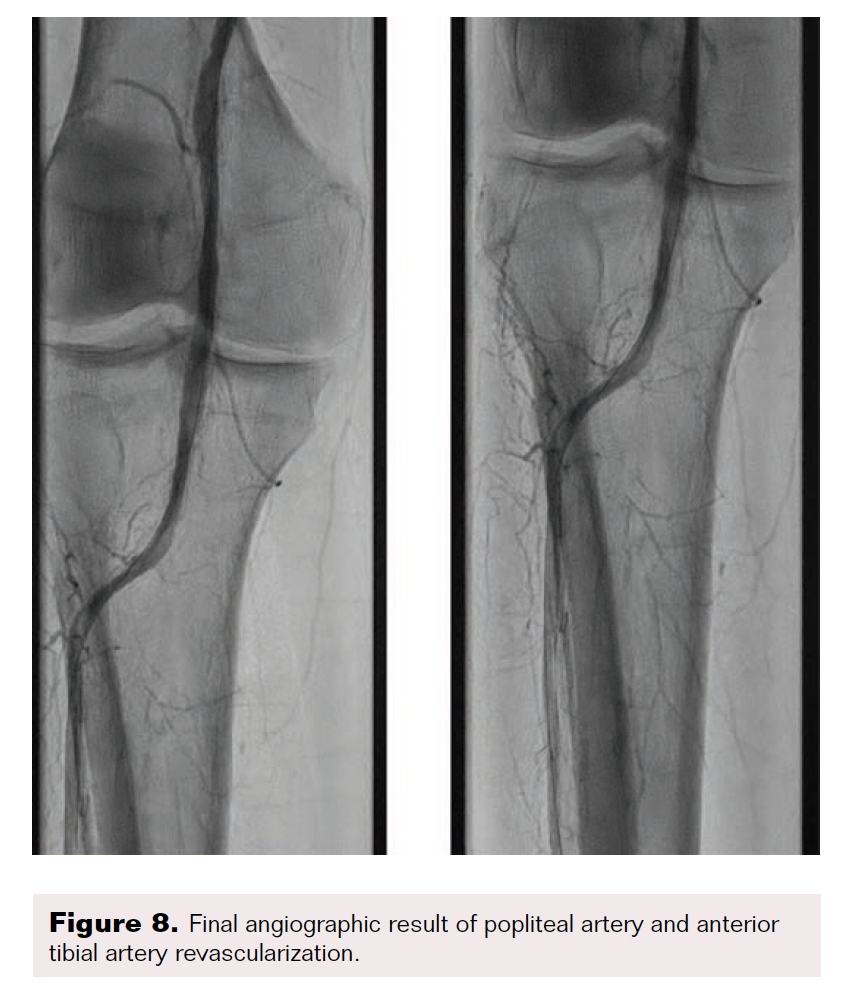

After the wire exchange, we attempted to aspirate, then flush, the 6F sheath with heparinized saline. After multiple failed attempts at sheath aspiration, we suspected a clotted arterial sheath and immediately proceeded to sheath exchange with a new 6F 45 cm sheath. Cautious to maintain wire position, the sheath was successfully exchanged. Saline flushing of the removed sheath resulted in expulsion of extensive clot burden (Figure 5). Repeat ACT confirmed therapeutic anticoagulation. The procedure concluded with percutaneous transluminal angioplasty followed by stenting of the SFA with BioMimics 6 x 150 mm stents (Figure 6). Final angiography demonstrated brisk flow through the SFA, popliteal, and anterior tibial arteries with no evidence of distal embolization (Figure 7 and Figure 8).